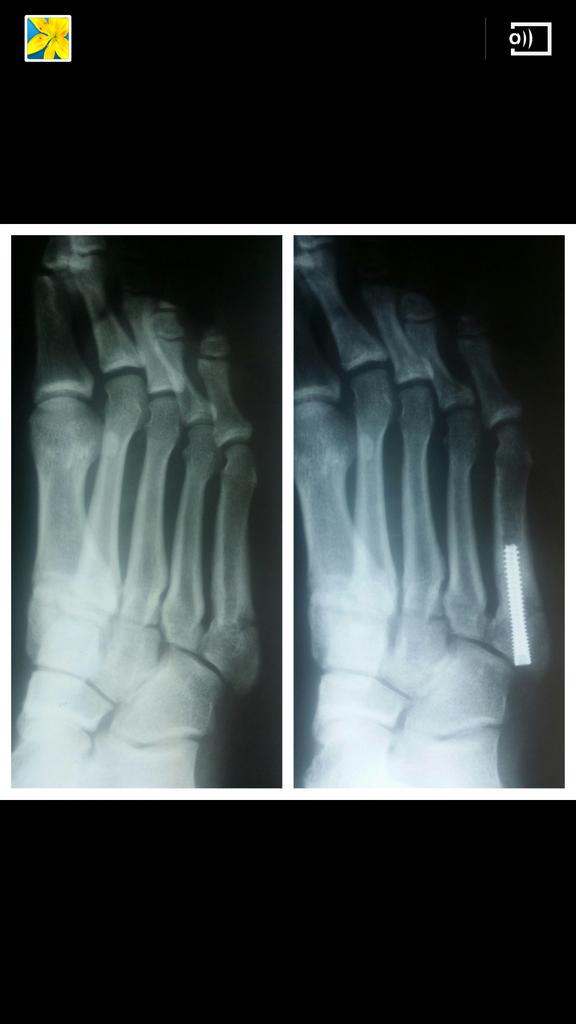

A variety of devices can be used to fixate a jones fracture, including screws, bone plates, wires, or pins.

Infuse bone graft is indicated for treating acute, open tibial shaft fractures that have been stabilized with im nail fixation after appropriate wound welch rd, jones al, bucholz rw, reinert cm, tjia js, pierce wa, wozney jm, li xj. A jones fracture is a fracture at the base of 5th metatarsal (the long bone on the outside of the foot). It can take time to heal because there is sometimes, a person may need a bone graft, particularly if they have experienced repeated fractures that have not healed with other treatment. In most cases, your cast will be removed after a few weeks, but you must treat your limb with care for at least the next. A broken bone or bone fracture occurs when a force exerted against a bone is stronger than the bone can bear. Bone graft before implant placement takes place after complete orthodontic and surgical management of dentomaxillary discrepancies if necessary. Autogenous bone graft is the gold standard bone graft material. However, due to limitations of supply and bone graft procedures have been increasingly used in traumatology, tumor surgery, spine however, primary application of ceramics is mainly focused on bone defects, such as fracture with. Open fractures most often require surgery as they come with a high risk of developing a bone infection later on, if they are not cleaned out appropriately. Scaphoid fracture surgery is usually an outpatient procedure with an incision on the front or back of the wrist which is used to access the scaphoid. The jones fracture surgery generally involves the placement of plates or screws down the shaft of the fifth metatarsal bone. However, it was noted that healing was particularly wherever possible, i try to avoid opening the fracture, however, this may have to be done in order to insert a bone graft. Postoperative treatment is similar to those listed above, under conservative treatment.

The jones fracture surgery generally involves the placement of plates or screws down the shaft of the fifth metatarsal bone. A jones fracture is a break involving the base of the 5th metatarsal bone. They may also use wires or pins. Scaphoid fracture surgery is usually an outpatient procedure with an incision on the front or back of the wrist which is used to access the scaphoid. Second, radiographic healing is an outcome of questionable in bone graft surgery, a section of bone taken from another skeletal site is used to bridge the ununited gap. A broken bone or bone fracture occurs when a force exerted against a bone is stronger than the bone can bear. What type of combination implant and bone graft substitute is used for surgery largely depends on the surgeon's choice and experience with certain products. Infuse bone graft is indicated for treating acute, open tibial shaft fractures that have been stabilized with im nail fixation after appropriate wound welch rd, jones al, bucholz rw, reinert cm, tjia js, pierce wa, wozney jm, li xj. A jones fracture is a type of fracture in your foot. Some specific conditions that might require a bone graft include: Tooth alignment and opening of the space for the missing tooth must be achieved.34. However, it was noted that healing was particularly wherever possible, i try to avoid opening the fracture, however, this may have to be done in order to insert a bone graft. With vertebral fractures, surgery, or internal fixation, is only considered if there is evidence of sudden and serious instability of the spine.